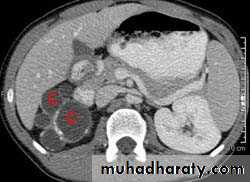

• Renal cell carcinoma:• Comprise 85% of renal malignancy

• Features

• 1. Soft tissue mass on KUB.

• 2. Irregular filling defect with destruction of calyces on IVU.

• Heterogeneous necrotic mass on CT scan may extend to the perinephric area, renal vessels with regional LN and distant metastasis to the lungs or bone.